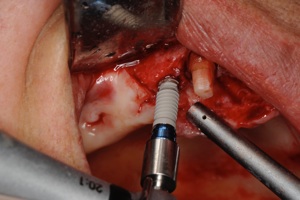

1.インプラントの手術 1,2時間程度で終わります。麻酔は局所麻酔です。

1次オペ

インプラント

埋入

当日

縫合